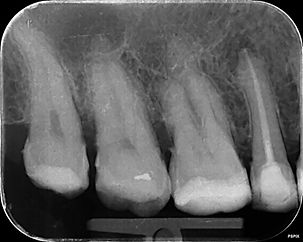

RCT LL6

Brefore

After

This gallery presents a selection of clinical radiographs (X-rays) from root canal treatments carried out by Stuart as part of his general dental practice. These images are shared to help illustrate the precision, planning, and attention to detail involved in modern endodontic care.

All images are anonymised and displayed for educational and illustrative purposes only.